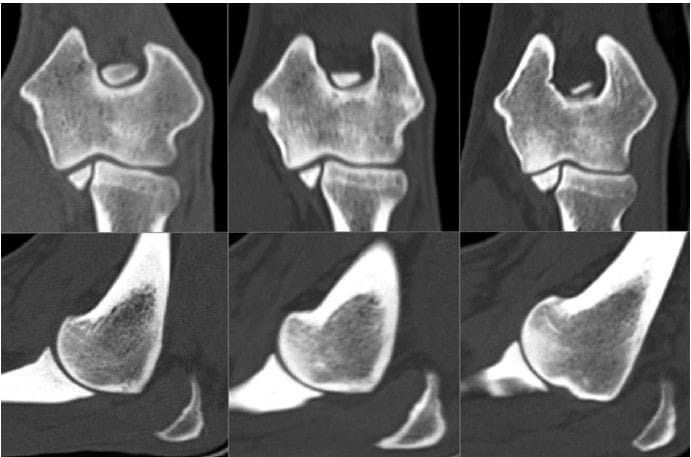

Reference images of sclerosis grade 0, grade 1, and grade 2 (left to right) of themedial aspect of the humeral condyle in the dorsal (top) and

sagittal (bottom) planes.